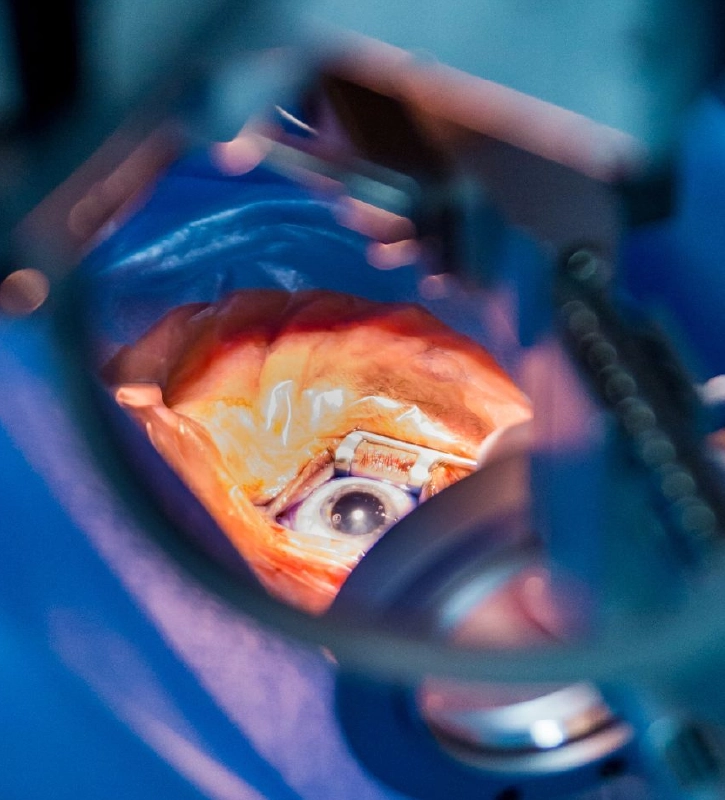

CIRUGÍA DE CATARATA

CIRUGÍA DE CATARATA

Usamos la última tecnología para eliminar las Cataratas de forma segura. Sin estadía.